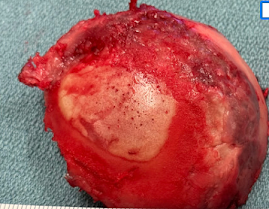

His humeral head showed the "Friar Tuck" pattern of central cartilage loss.